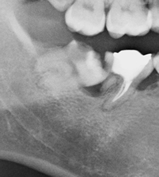

親知らずが骨の中に埋まっている場合には、局所麻酔を行い、歯肉を切開し、歯の周囲の骨を削除します。傾斜している親知らずの場合には、歯を分割して抜歯します。抜歯後は縫合し、翌日に消毒、1週間後に抜糸します。通常は外来通院で行いますが、歯が深く骨に埋まっている場合には、入院全身麻酔下で行うこともあります。